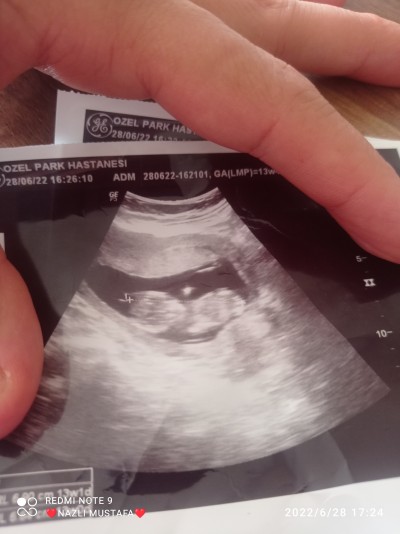

Bir türlü ogrenmedin ya gostermeyor doktorda demiyor lutfen yardimci olun

Gebelik haftası 13

Bacak arası olması lazım anlamak için bu şekilde belli değil

Bacak arası kapali

Kafa yapısı kızlara benziyor crls nedir

6.80 crl

Kız bence benim kızımın crls aynı ve kafa yapısı da aynı Bnim 15.4 günlük

Daha erken zaten doktor birşey dese bile kesin olmaz 20 haftadan sonra kesin sonucu alabilirsin